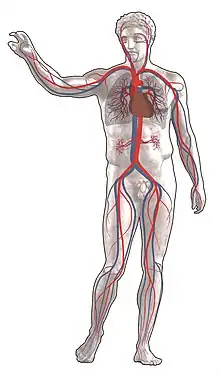

Appareil cardiovasculaire

L'appareil cardiovasculaire, appareil circulatoire ou système sanguin, est un système circulatoire en circuit fermé qui assure le transport du sang du cœur vers les extrémités et les divers organes et, en retour, de ceux-ci vers le cœur. Il est constitué du cœur et des vaisseaux sanguins qui forment le système vasculaire, les vaisseaux lymphatiques qui composent le système lymphatique lui étant parfois associé.

L'appareil cardiovasculaire a pour fonction d'apporter aux différentes cellules les nutriments et le dioxygène dont elles ont besoin et d'éliminer leurs déchets comme le dioxyde de carbone. Cette circulation continue fonctionne grâce à des vaisseaux sanguins et une pompe : le cœur. On appelle artères les vaisseaux apportant le sang du cœur vers les tissus tandis que les veines apportent le sang des tissus vers le cœur.

On distingue la circulation systémique (grande circulation), dont le rôle est de recharger les muscles et organes en dioxygène et en nutriments et la circulation pulmonaire (petite circulation) dont le rôle est d'assurer la ré-oxygénation du sang par les poumons et l'élimination par ceux-ci du dioxyde de carbone (hématose).

Dans la grande circulation, le ventricule gauche du cœur expulse le sang via l'artère aorte vers les capillaires des différents organes où s'effectuent divers échanges. L'aorte est une artère élastique et épaisse capable de résister aux hautes pressions lors de la contraction cardiaque. Son élasticité contribue à la restitution d'un débit continu alors que les contractions cardiaques sont discontinues. Le sang est ensuite ramené au cœur droit via les veines caves supérieure et inférieure.

Dans la petite circulation, le ventricule droit du cœur propulse le sang via l'artère pulmonaire vers les poumons. Le ventricule droit est moins épais que le gauche car il doit seulement assurer la vascularisation d'une partie restreinte du corps.

Ainsi, dans la circulation systémique, les artères apportent du sang oxygéné aux tissus et les veines ramènent du sang appauvri en oxygène vers le cœur ; dans la circulation pulmonaire, les artères pulmonaires transportent du sang pauvre en dioxygène et les veines pulmonaires du sang riche en dioxygène.